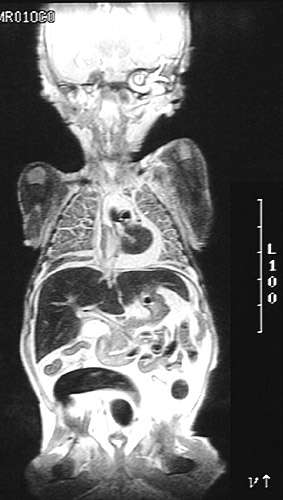

| This T2 weighted MRI scan of a neonate in coronal view demonstrates a bright pericardial effusion around the heart. There is also ascites with bright bright fluid in the peritoneal cavity. Such effusions can occur with hydrops as well as heart failure from anemia, infection, and congenital anomalies. |